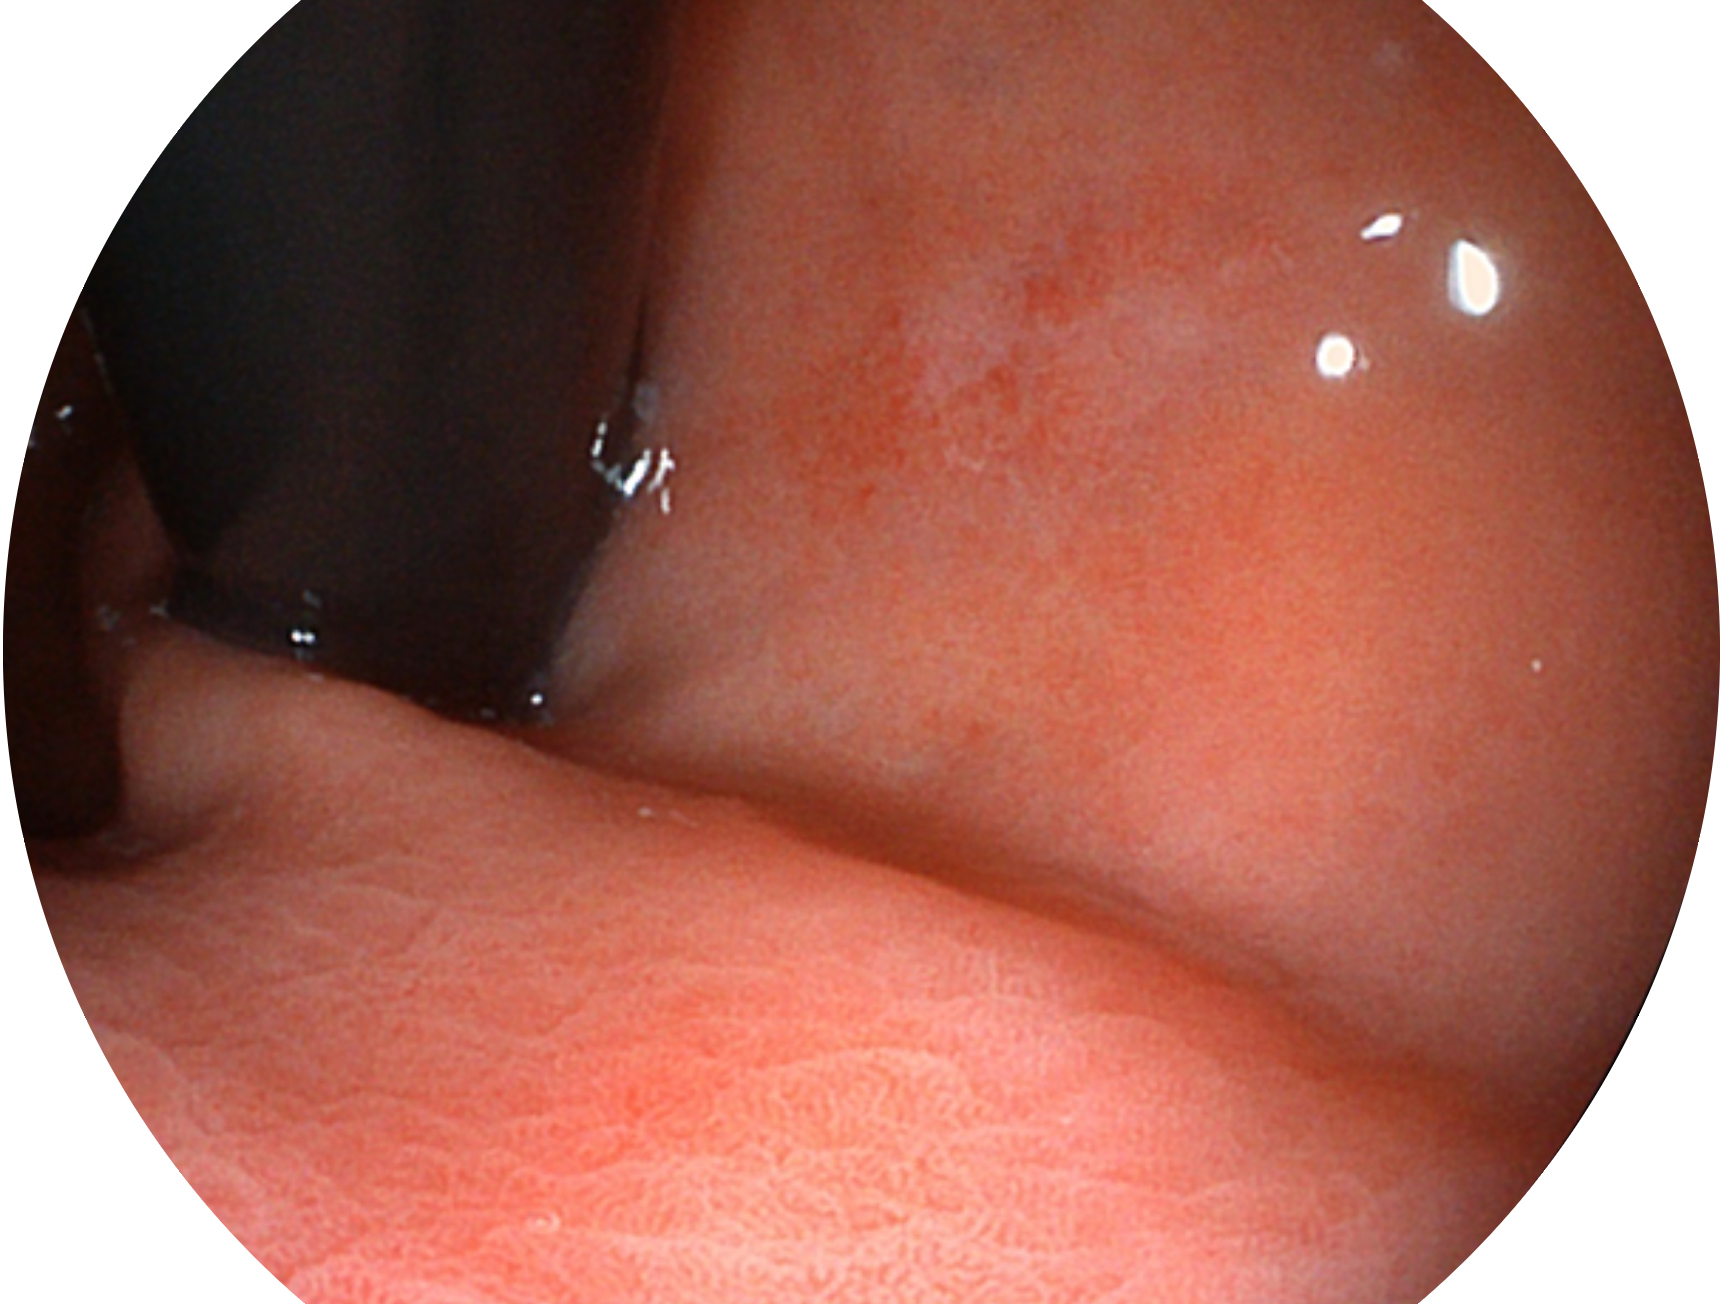

米兰官方网站新开发的内镜染色技术,主要是基于多波长LED 光源的开发,VLS-55Q 四波长LED 光源是由四个不同颜色的LED光按照相应照明模式所规定的特定发光比例进行合束后形成,合束后形成的照明光的光谱由红光、绿光、蓝光及蓝紫光这四个不同的波段范围构成。具有更高光谱自由度,通过光谱比例的控制,实现了聚谱成像技术,英文全称为“Spectral Focused Imaging, SFI”,缩写为“SFI”和光电复合染色成像技术,英文全称为“Versatile Intelligent Staining Technology, VIST”,缩写为“VIST”。